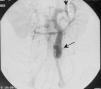

Pacientes y métodosCaso 1Varón de 2 meses de edad derivado para estudio de cardiopatía. Durante la exploración clínica se auscultó soplo mesocárdico ll/lV, cardiomegalia e HTA en extremidades superiores e imperceptibles en extremidades inferiores. Los estudios iniciales demostraron deterioro de la función renal (filtrado glomerular [FG] de 34ml/min/1,73m2 y proteinuria de 55mg/m2/h), elevación de los valores de angiotensina I en plasma de 200 ng/ml/h (VN: < 40) y de aldosterona en 339,2μg/dl (VN: 6-25), electrocardiograma con hipertrofia biventricular con signos de isquemia y ecocardiografía con miocardiopatía hipertrófica, estudio hemodinámico cardiaco con leve coartación aórtica y mínima estenosis valvular. Por aortografía descendente se observó hipoplasia de la aorta infradiafragmática precedida por un aneurisma por encima del origen del tronco celiaco (TC) e hipoperfusión de ambos riñones (fig. 1). La ecografía renal y la urografía intravenosa fueron normales.

A los 6 meses de edad se practicó un aortografía constatando aorta abdominal hipoplásica por debajo de la salida de la AMS (fig. 6). El territorio iliaco se repermeabilizaba a través de la hipogástrica y la femoral común derecha.